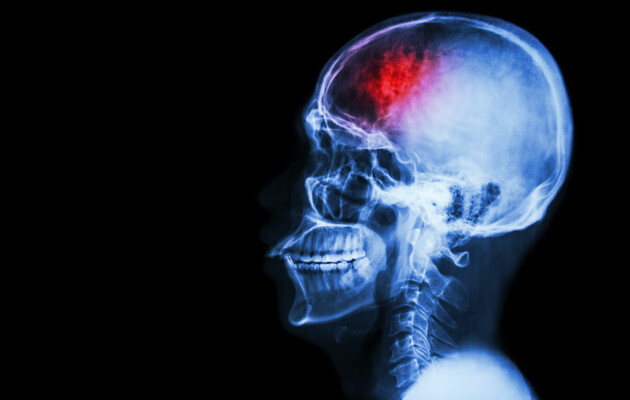

29 жовтня відзначали Всесвітній день боротьби з інсультом. Кожного року понад 100 українців помирають через інсульт, третина з них – молодше 65 років. Фахівці Центру громадського здоров'я (ЦГЗ) розповіли, як розпізнати симптоми інсульту та що робити до приїзду лікаря.